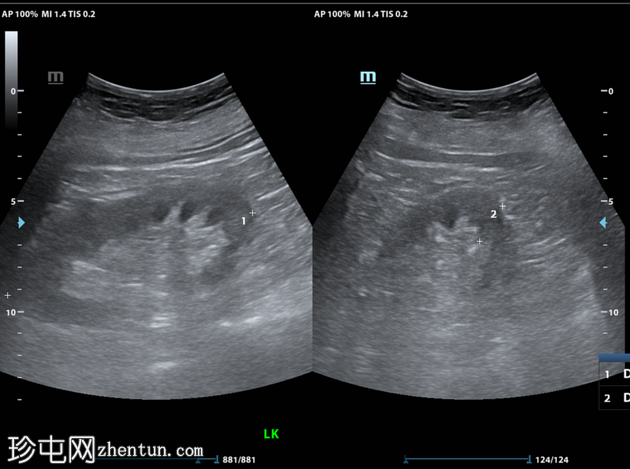

X线检查

右侧膈肌下方可见斑驳状气体影。

野清晰。无胸腔积液。心纵隔边界正常。

对于发热患者,若在右侧膈肌下方发现斑驳状气体影,放射科医生应考虑气肿性肝脓肿的诊断。鉴别诊断包括膈下脓肿。门静脉积气或胆道积气的可能性较小,因为它们呈管状。其他良性鉴别诊断包括 Chilaiditi 综合征。